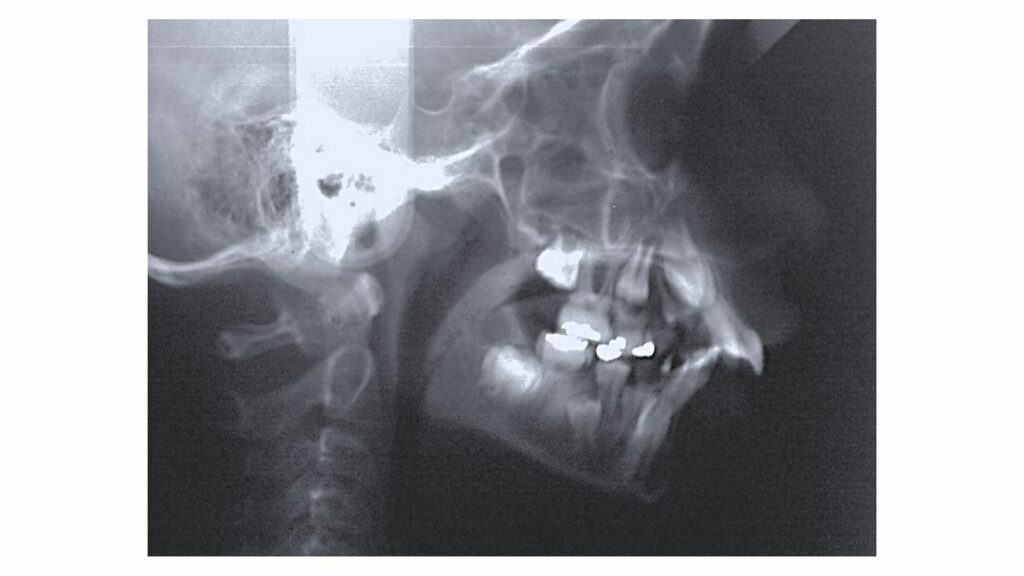

A análise e classificação do tipo facial e da musculatura do paciente é essencial para o planejamento e execução do tratamento. Pacientes com musculatura mais forte são tratados de forma diferente daqueles com musculatura mais suave, garantindo um tratamento mais eficaz e confortável.